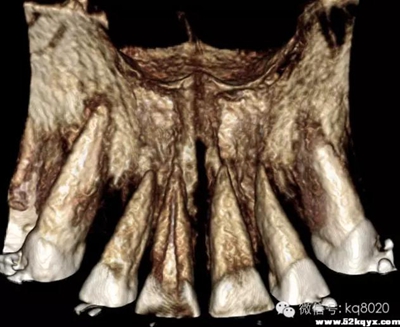

上下頜前牙區(qū)(11、12或者23之間,具體根據(jù)CT和患者頜關系決定):

危險因素:此處無重要血管神經(jīng),相對安全,但牙根間距較小,避免傷及牙根植入位置和角度:應從膜齦聯(lián)合處或其牙合方植入,大約距離牙槽嵴頂5-6mm的位置,

原因

①此處牙根間隔最大;

②避免植入后粘膜覆蓋;支抗釘位于牙根之間,與牙體長軸成30-45°角

大?。河捎谇把绤^(qū)牙根間距小,骨質(zhì)疏松,宜選用6×1.4mm,且無切削尖設計支抗釘